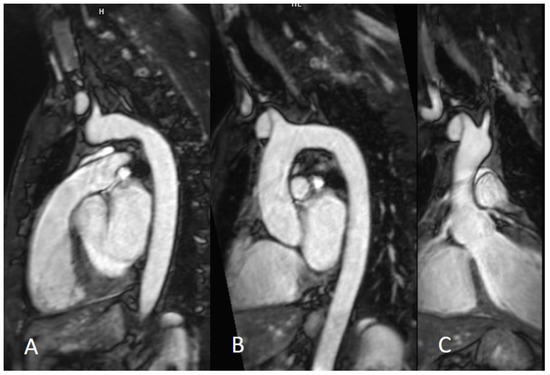

Figure 5.

Three-dimensional navigator whole-heart CMRA sequence. The 3D CMRA allows to acquire the whole heart in a gated free-breathing acquisition (A), with the possibility of subsequent MPR reconstructions (B,C). CMRA—coronary magnetic resonance angiography; MPR—Multiplanar reconstruction.